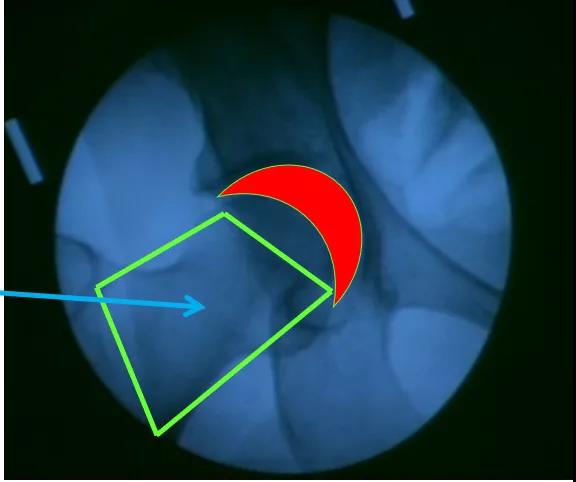

髋关节穿刺注射部位理想进针区域:牵引下C臂机透视关节间隙“新月征”

高难度红色区域:无牵引、无C臂机容易进针安全区域:绿色框内